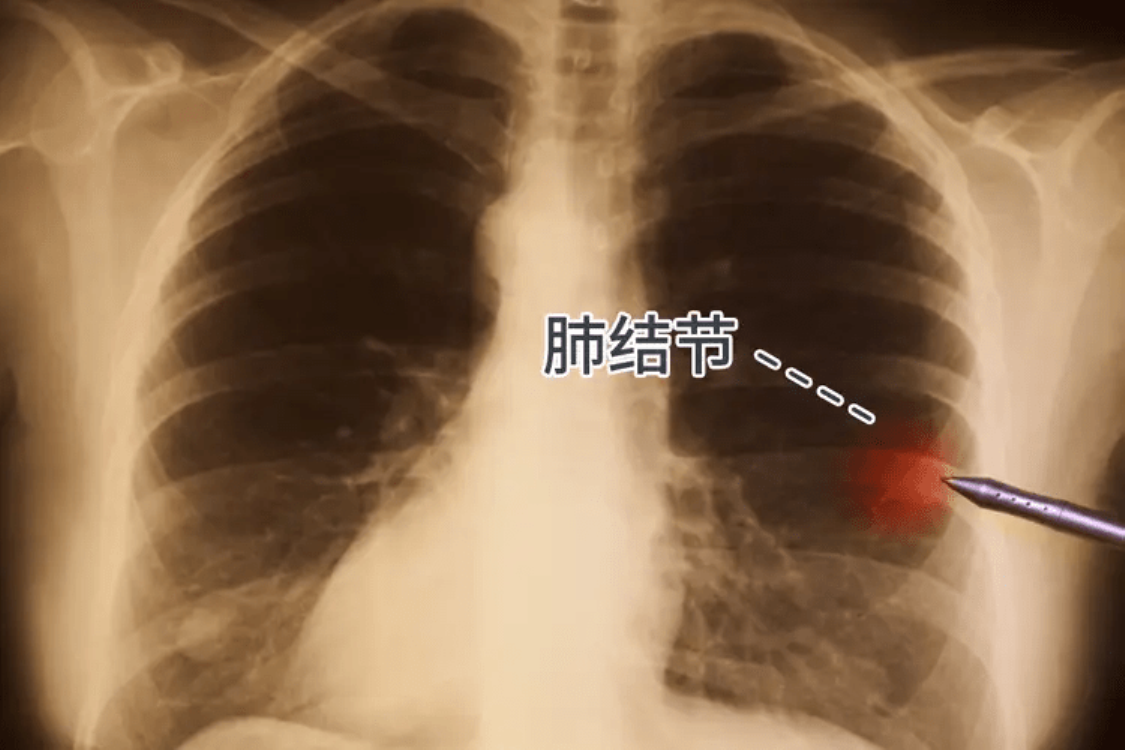

Loại u phổi nào an toàn?

Có u ở phổi có nghĩa là bị ung thư phổi? Tất nhiên là không. Các u con gọi là hạch phổi thực chất là thuật ngữ hình ảnh, dùng để chỉ các hình đặc tròn khu trú với nhiều kích cỡ khác nhau, có viền rõ hoặc mờ và đường kính nhỏ hơn hoặc bằng 3 cm trên hình ảnh chụp CT phổi.

Hầu hết chúng là những tổn thương lành tính và chỉ một số ít là khối u ác tính. Ung thư phổi có thể biểu hiện dưới dạng các hạch ở phổi, nhưng không phải tất cả các hạch ở phổi đều là ung thư phổi hoặc sẽ trở thành ung thư phổi.

Vậy loại u phổi nào tương đối an toàn? Nói chung, đối với các hạch tương đối nhỏ (dưới 6 mm), không có đặc điểm ác tính điển hình trên hình ảnh (chia nhánh, có gờ, rỗng trong, xuyên cắt mạch máu, v.v.). Đồng thời xét nghiệm máu hạch phổi 7 kháng thể cho kết quả âm tính thì những hạch nhỏ như vậy có thể nói là những nốt sần “đẹp và nhân hậu”, rất ít có khả năng trở thành ung thư.